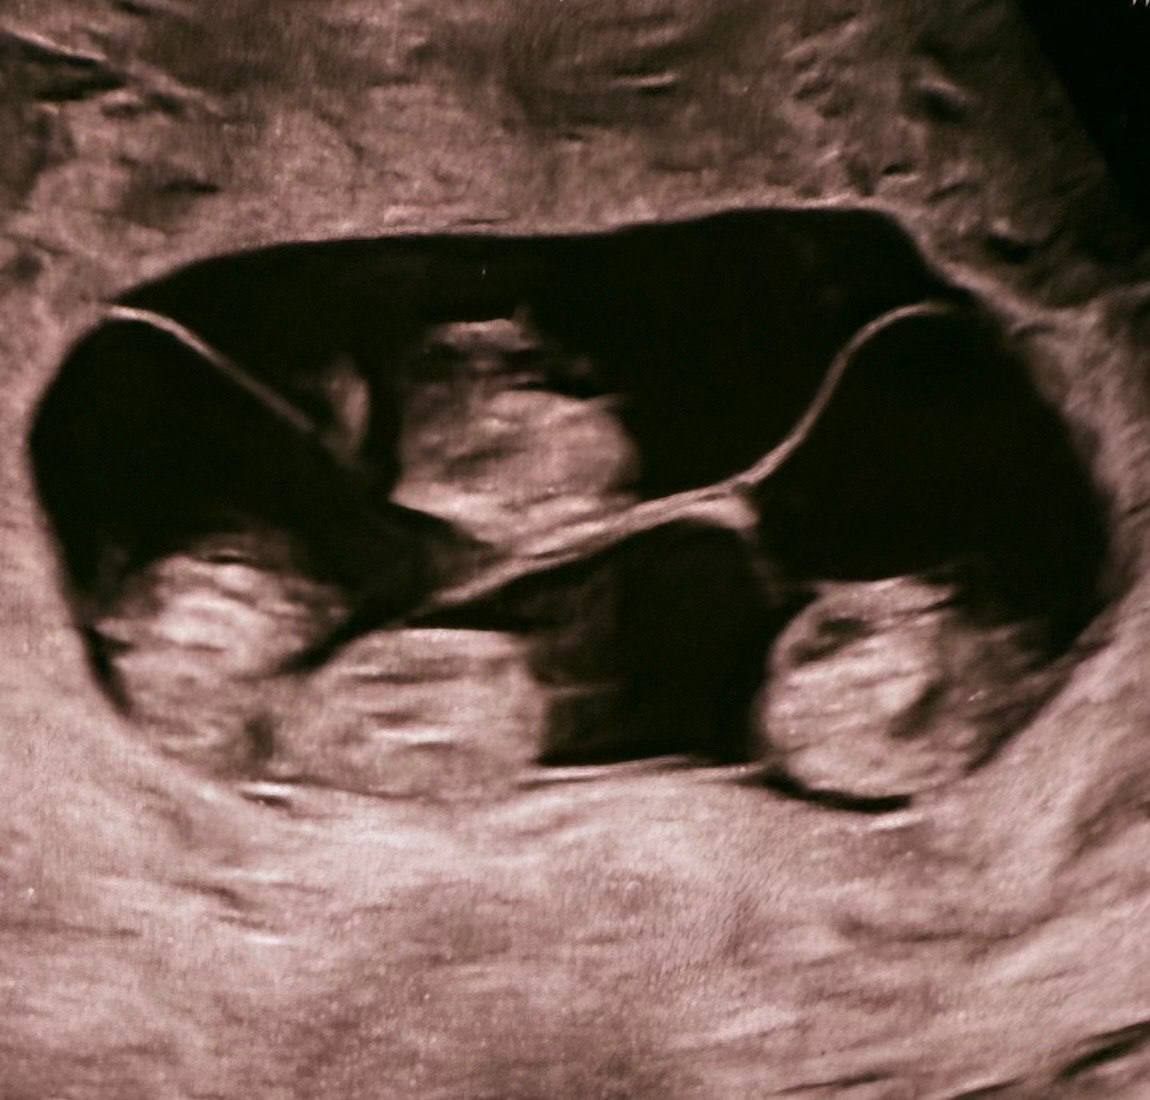

В России впервые зафиксировали рождение однояйцевой четверни — подобные случаи встречаются примерно раз на 15,5 миллионов родов!

Малышки появились на свет в Санкт-Петербурге на 32-й неделе беременности. Их вес — от 1360 до 1640 граммов, рост — от 37 до 41 сантиметра.

В мире известно около 15 случаев рождения идентичных четверняшек, и большинство из них — девочки. Сейчас новорождённые находятся под наблюдением врачей.